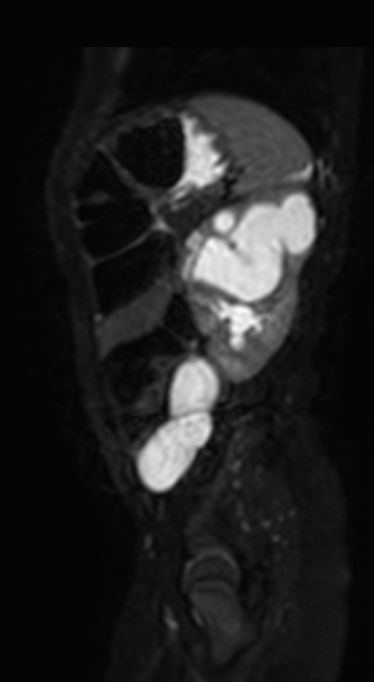

Sagittal T2w MultiVane XD SPAIR